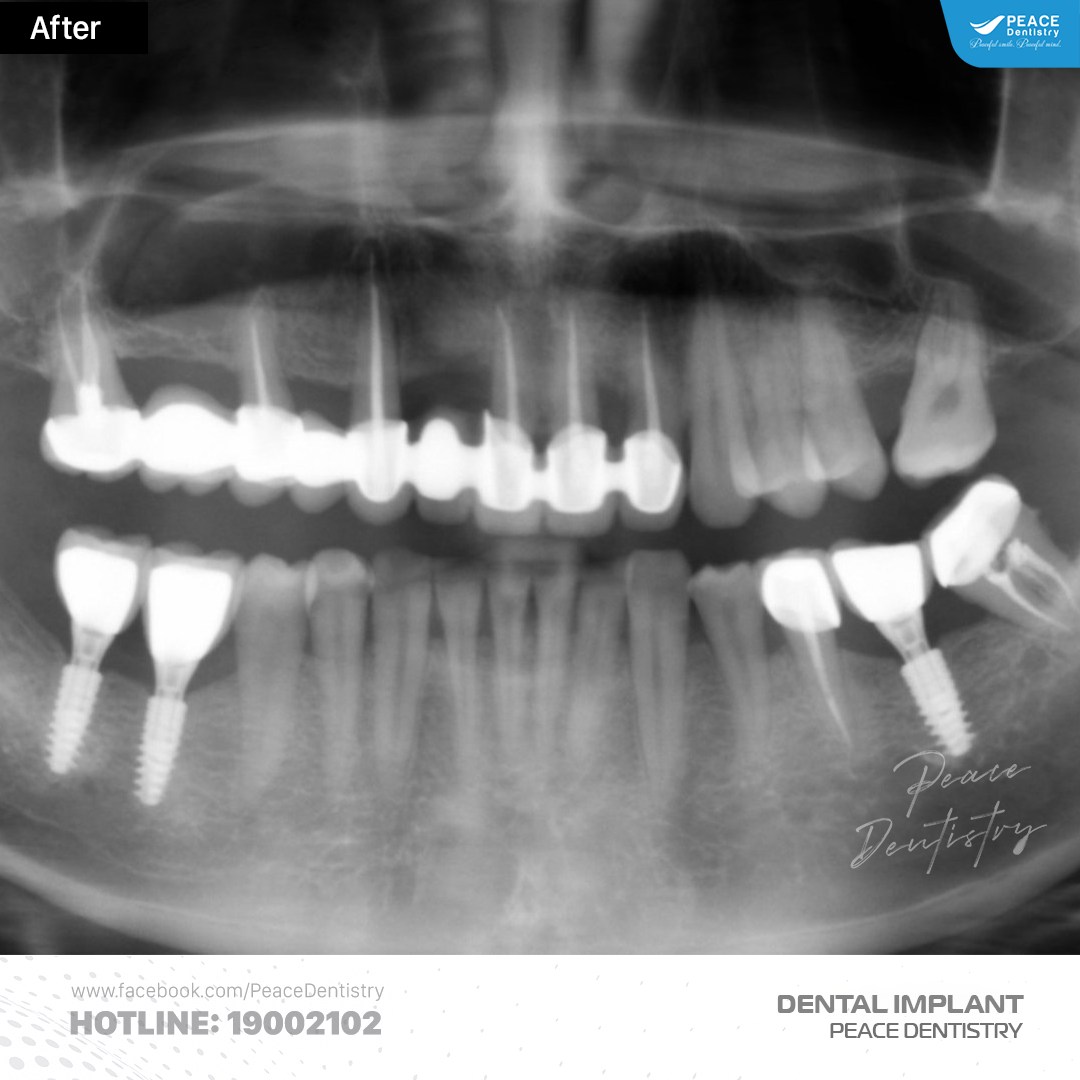

(Hình ảnh khách hàng tái khám implant sau 5 năm tại Peace Dentistry)(**)

(Hình ảnh khách hàng tái khám implant sau 10 năm tại Peace Dentistry)(**)